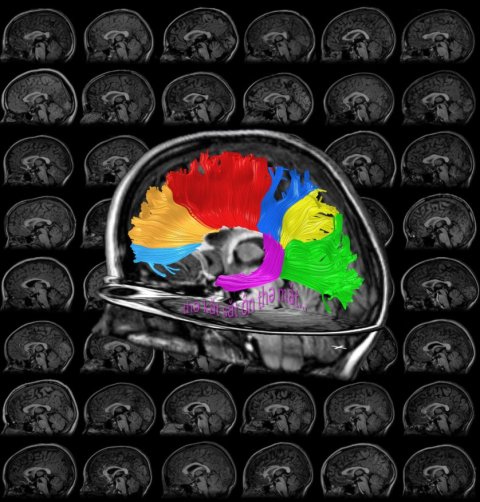

Reading is an amazing skill that many people master. Watch as a person's eyes dart across the page while they read. The precision and speed of these eye movements- planned on the fly with split-second timing- is on par with the skill of an athlete executing a sophisticated maneuver. As with sports, becoming a skilled reader is not something that everyone finds easy. For some, learning to read with moderate proficiency is a painful ordeal that requires extraordinary effort. By studying brain structure and function, I hope to understand why learning to read easy for some children and difficult for others.

Cortical regions activated by a reading task in a child's brain

My collegues Brian Wandell, Michal Ben-Shachar, Gayle Deutsch, and I have recently published a set of papers describing our recent work on reading development. See my publication list for links to these papers.